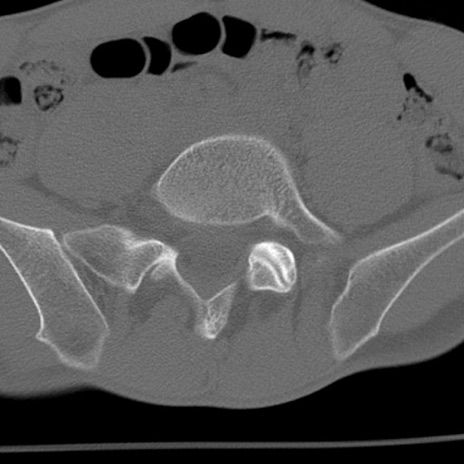

症例3 腰椎CT(横断像)

腰椎CT